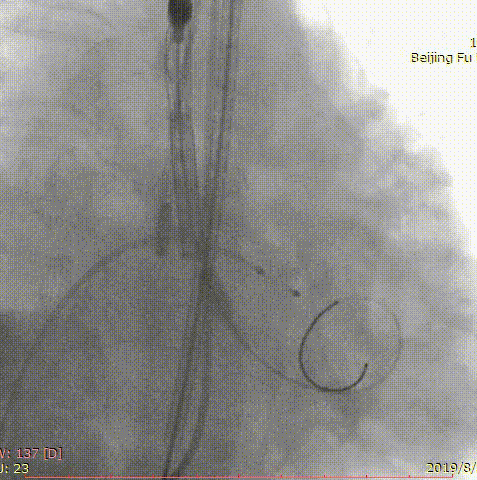

第二位患者是一名84岁男性,因发现心脏瓣膜异常12年,胸闷气短5年入院。曾于我院就诊,超声心动图提示主动脉瓣重度狭窄,2年前行经导管主动脉瓣球囊扩张术,术后患者仍有气短症状反复发作。此次入院后超声心动图提示主动脉瓣球囊扩张术后、主动脉瓣重度狭窄并少量反流,主动脉瓣平均跨瓣压差97mm,收缩期峰值流速6.3m/s,最大压差158.8mmHg。患者高龄、虚弱、消瘦(BMI仅18lg/m2),术前CT评估患者呈带嵴二叶瓣,L-R融合,主动脉瓣环21*29.6mm,周长80.6mm,面积494.7mm2,瓣上多平面测量结果如下。

右侧股动脉为主入路,应用20mm微创心通敖广球囊预扩张,植入24mm微创心通Vifaflow瓣膜,但术中造影提示瓣膜打开不理想,遂应用20*40mm球囊后扩张,术后造影提示无瓣周漏,超声提示主动脉瓣跨瓣压差仅2mmHg。

术前影像